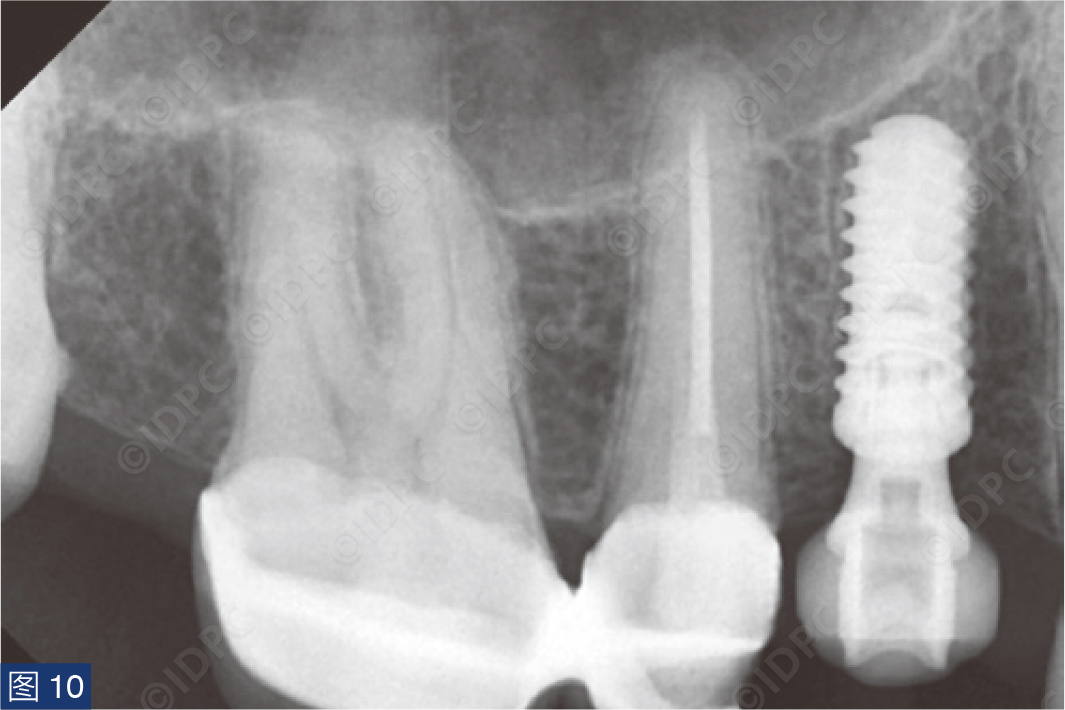

个性化愈合基台通过将树脂材料粘固至钛基底上制成,用于在愈合期间调节软组织形态(图8)。个性化的愈合基台模仿所谓的“郁金香形状”,以创造更理想的穿龈轮廓。使用6-0不可吸收单丝线(Optilene,B. Braun公司)无张力缝合固定软组织(图9a、9b)。术后X线片显示植体与邻牙平行放置(图10)。向患者提供术后指导,以保持植入部位的口腔卫生。

在exocad软件(exocad公司)上进行全数字化修复流程设计,在copaSKY uni.fit钛基底(bredent medical公司)上制作完成螺丝固位氧化锆混合陶瓷一体冠。种植位点显示出足够的颊侧软组织厚度(图12a)及良好的牙龈轮廓(图12b)。取下个性化愈合基台后,种植体周围软组织健康(图13、14),此外,取下后立即进行术前口内扫描以记录软组织轮廓。随后放置扫描体并进行数字印模以记录种植体位置(图15)。同时扫描对颌牙弓及咬合信息。获得的STL文件以数字方式发送至技工室。技工室在钛基底上完成聚甲基丙烯酸甲酯(PMMA)材料的试戴牙冠,以检查邻接和边缘密合情况,同时调整咬合(图16、17)。一旦完成所有调整,进行重新扫描。最终在钛基底上完成螺丝固位的全结构氧化锆混合陶瓷修复体,与牙龈接触的修复体表面高度抛光(图18),并以25 Ncm戴入口内。修复体实现了出色的颜色匹配及临床结果(图19)。螺丝孔用聚四氟乙烯填塞并用树脂材料密封(图20)。术后对照X线片显示修复体正确就位(图21)。六个月复查,增加的软组织轮廓清晰可见,牙槽骨水平保持稳定(图22-24)。